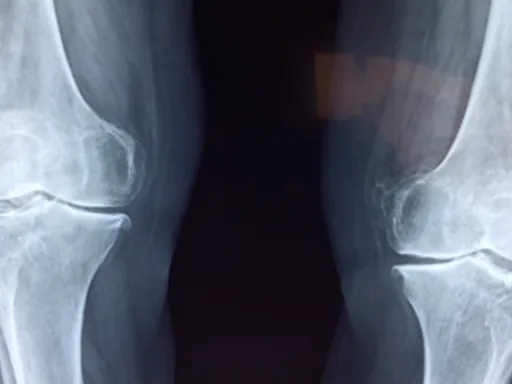

퇴행성 질환

다음으로는 퇴행성 질환이 있습니다. 나이가 들어감에 따라 무릎 관절의 연골이 마모되며, 이는 골관절염이라는 질환을 초래할 수 있습니다. 예를 들어, 65세 이상의 인구 중 골관절염을 앓고 있는 비율이 50%에 달하기도 하죠. 나이가 많을수록 관절이 약해지고, 이는 통증으로 이어질 수밖에 없어요. 😢

무릎 통증은 일상생활에서 많은 사람들에게 영향을 미치는 문제입니다. 그 배경에는 다양한 질병들이 있죠. 노화나 유전적 요인에 따라 발생하는 퇴행성 관절염은 대표적인 원인 중 하나입니다. 연구에 따르면, 65세 이상의 인구 중 약 50%가 퇴행성 관절염으로 인한 무릎 통증을 경험한다고 합니다. 이런 통증은 뼈와 연골의 마모로 인해 발생하며, 긴 시간 동안 지속적으로 통증을 유발할 수 있습니다.